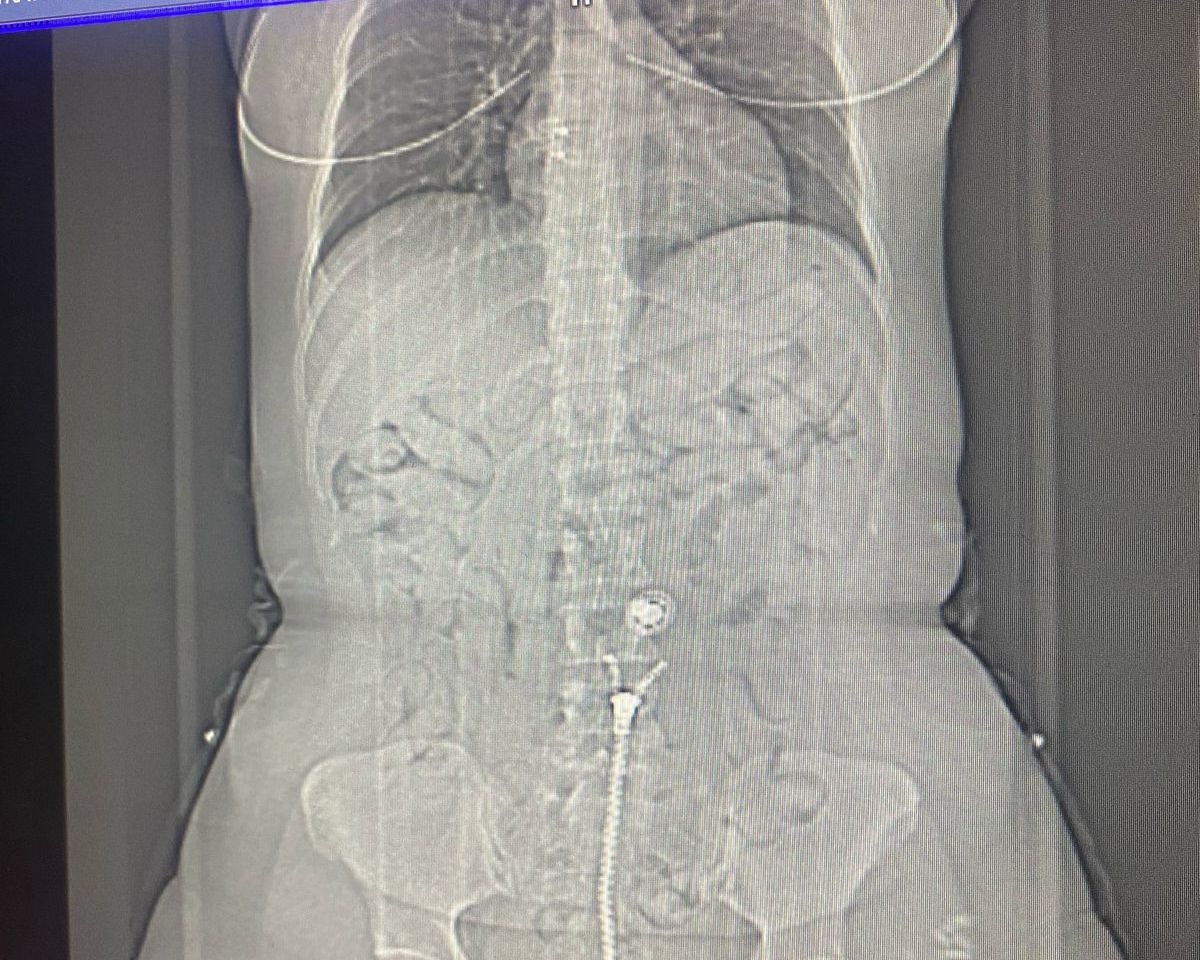

A mulher brasileira também confessou ter cerca de 80 outras cápsulas no estômago. A suspeita foi conduzida até a emergência do Hospital Metropolitano de Belém para retirar as drogas.

Drogas encontradas em posse da brasileira.